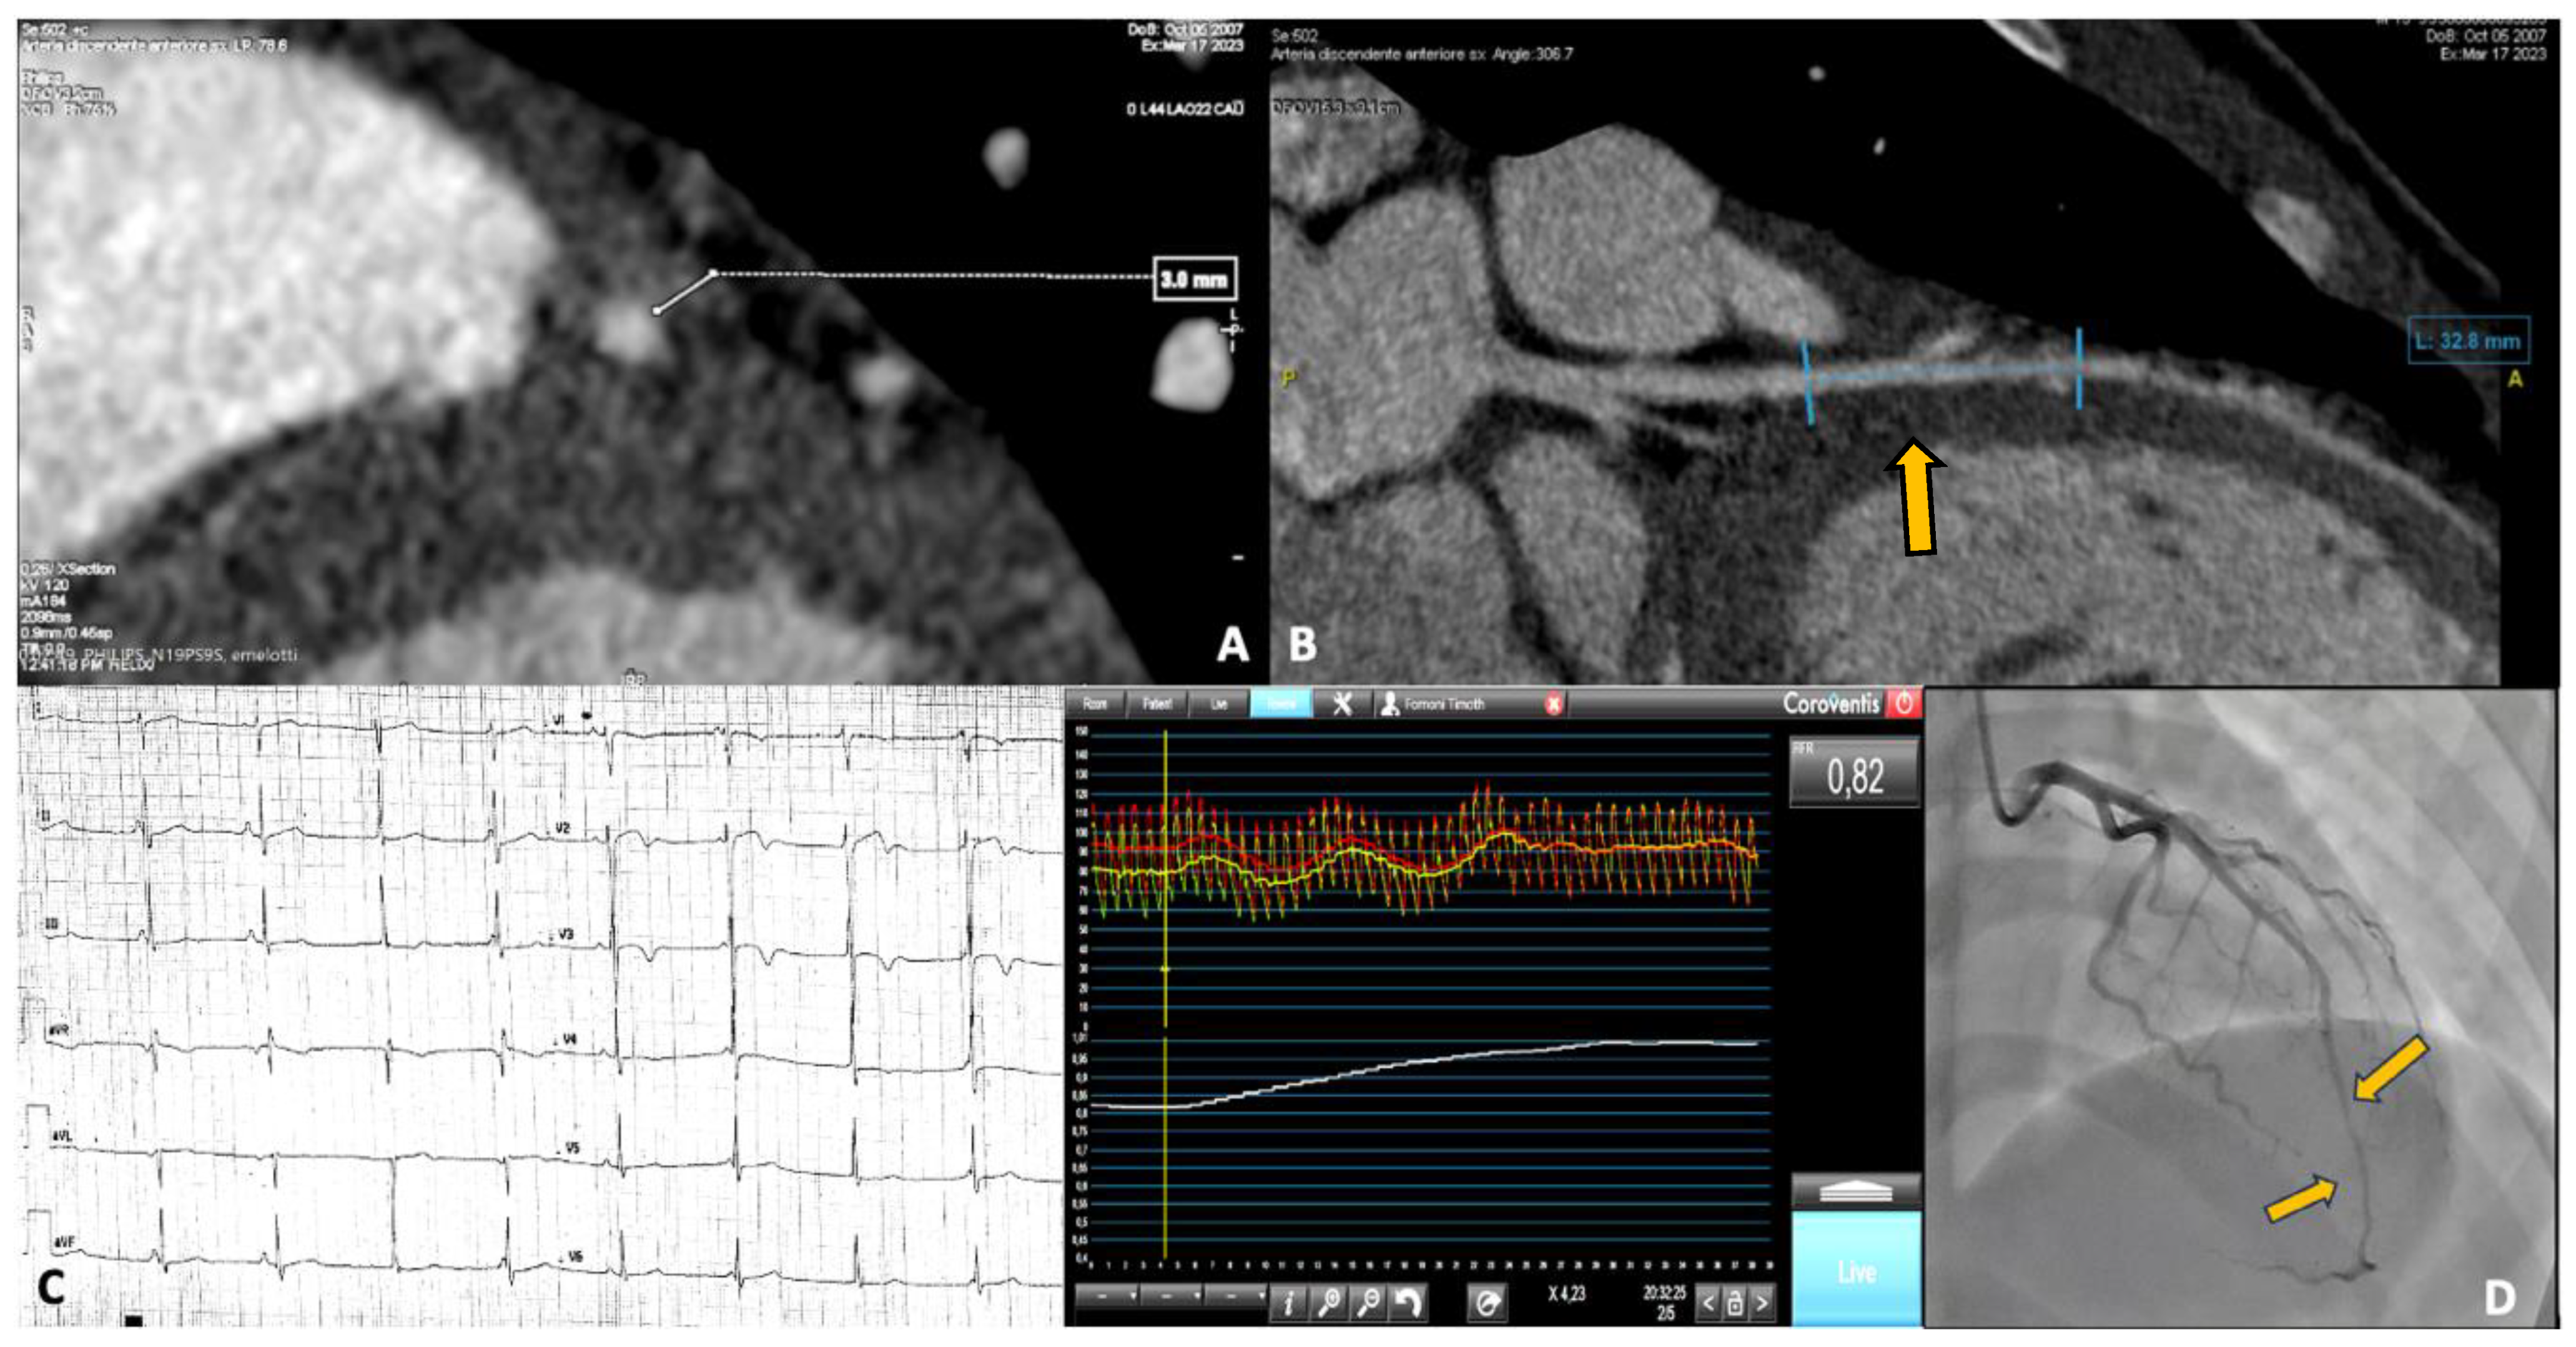

3.2. Case 2: Myocardial Bridge Presented as NSTEMI

4.1. Intramyocardial Bridge